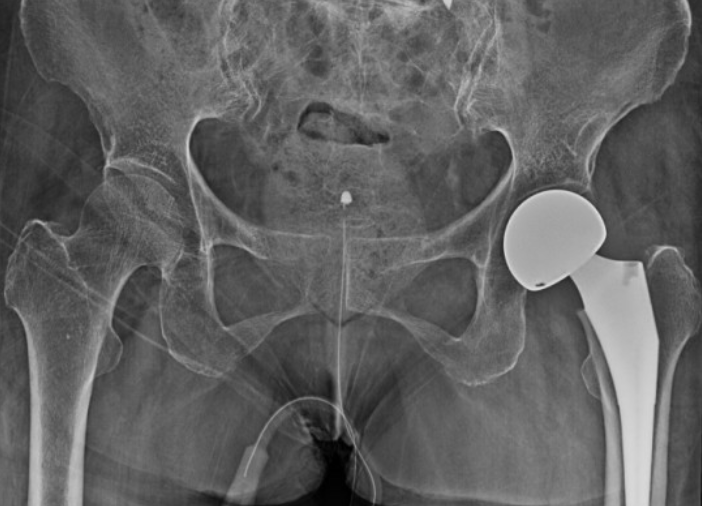

| 인공관절 치환술 | 손상된 관절을 인공관절로 교체하는 수술 |

| 부분 치환술 | 손상된 부위만 선택적으로 교체하는 방법 |